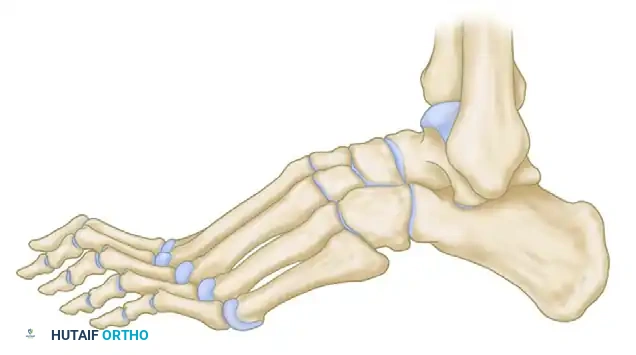

Key radiographic parameters include:

* Meary’s Angle (Talus-First Metatarsal Angle): Normally 0 degrees. In a cavus foot, the angle is increased, with the apex directed dorsally.

* Hibbs Angle: Intersection of the longitudinal axis of the calcaneus and the first metatarsal. Normal is < 45 degrees; it approaches 90 degrees in severe cavus.

* Calcaneal Pitch: Measures the degree of calcaneal deformity. Normal is 20-30 degrees.

Normal calcaneal pitch, but forefoot equinus in a patient with Charcot-Marie-Tooth disease. The calcaneal pitch angle measures the degree of calcaneus deformity.

In CMT, patients typically exhibit forefoot equinus with a relatively normal calcaneal pitch. In contrast, post-polio patients often present with a severe calcaneocavus deformity characterized by a drastically increased calcaneal pitch.

Calcaneal pitch variations in idiopathic and postpoliomyelitis deformities.